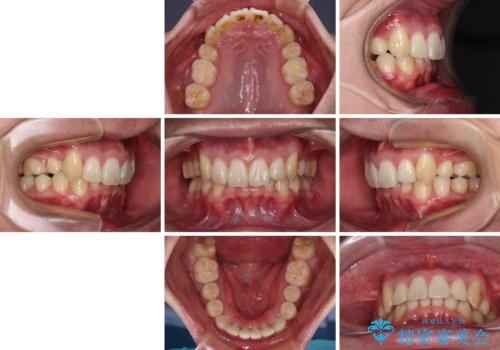

ディープバイトや奥歯の咬み合わせなど、インビザライン矯正では限界がありワイヤー装置での治療に及ばない仕上がりとなりました。

ただし、患者様としては八重歯や、それに伴う唇の閉じにくさが改善されたとのことで、納得いく状態での治療終了となりました。